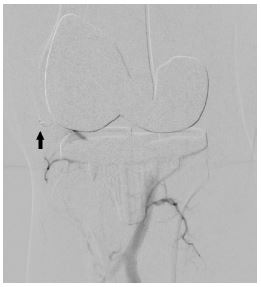

In view of continued knee joint swelling, the patient underwent right lower limb angiography the following week through the right femoral artery approach which identified a Pseudoaneurysm arising from the inferior medial genicular artery. This was embolized using 250 microns’ particles- embospheres and 2mm push able coils. Selective angiogram performed from superior medial and lateral genicular artery showed abnormal blush and pruning was done using 250-micron embospheres (Figures 3,4 & 5). An Ice pack was placed over the knee while instilling embolic agent particles to cause vasoconstriction of the skin arterial supply to avoid ischemia.

Figure 4: Post-operative Anteroposterior and lateral radiographs of Knee showing total knee replacement in place and gross joint eff usion in form of loss supra and infra patellar fat pad.